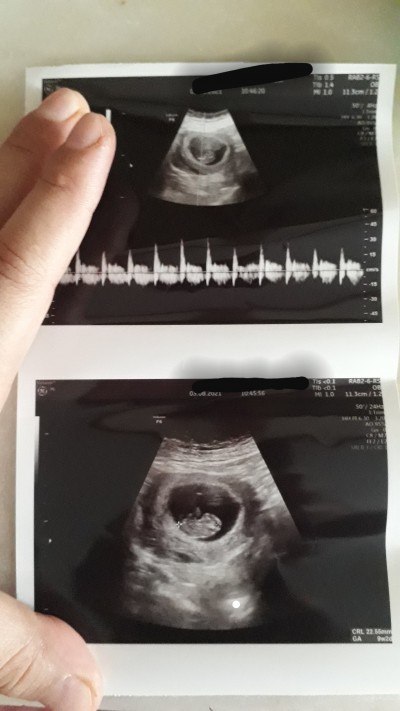

Kızlar merhaba biz 9 haftalik odlum fun kontrole gittik kalp atışı için. Cinsiyet tahmin etmek isteyenler buyursun atış serbest ama tecrubeli olanları da beklerim ☺☺

Genelde yuvarlak keseye kız fasulye gibi olanada erkek diyolar ama bilemedim içimden kız geçti canım sağlıkla doğsun inşallah :)

Kese kıza benziyor gibi. Sağlıkla gelsin minnak

Bende keseden tahmin edim oglumun kesesine benziyor kizimki daha yuvarlaldi

Kız kalp ayısı kac dakikada 141 den asagı kız yukarı erkek derler